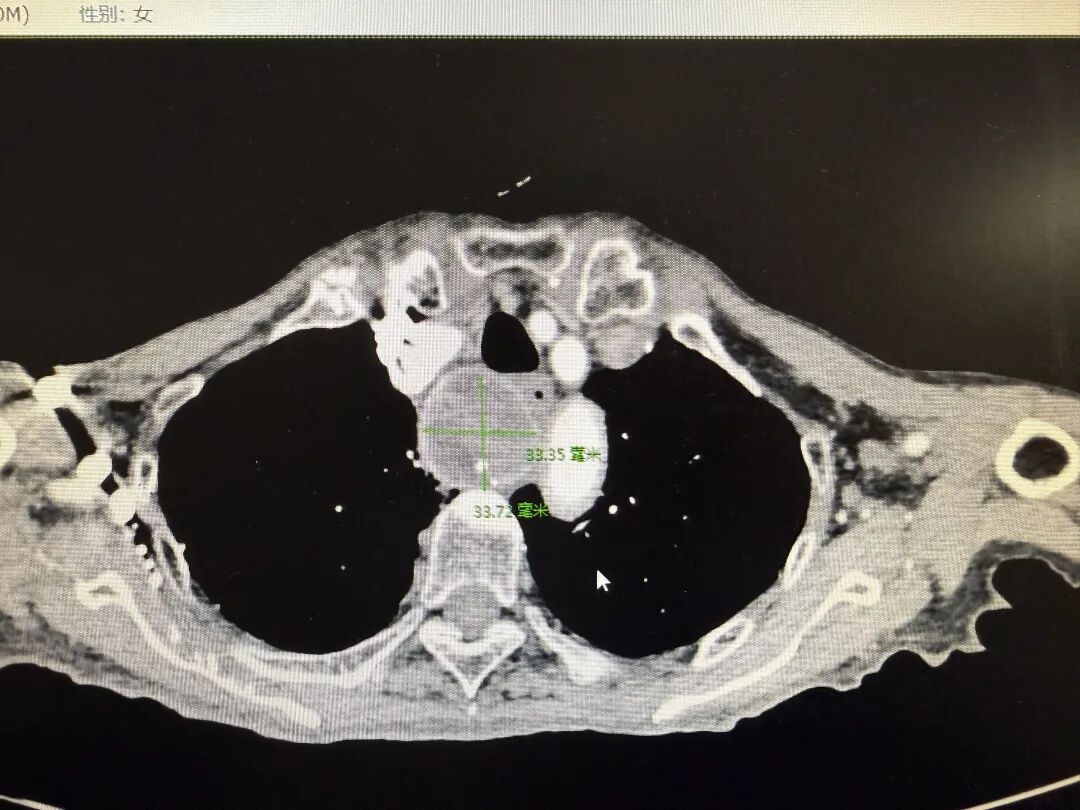

3月12日,潘老太再次气急发作,由急诊收住我院呼吸与危重症医学科,呼吸与危重症医学科结合病情后联系普外二科王俊磊参与会诊。王俊磊敏锐地发现那颗此前被发现的胸骨后巨大甲状腺,体积持续增大,像一块沉重的“石头”,死死压迫着气管和食管,这才导致老人呼吸、吞咽都备受阻碍,症状日渐加重。

全麻状态下,普外二科甲乳团队与王瞿辉主任密切配合、精准操作,小心翼翼地剥离胸骨后巨大的甲状腺组织,避开周围复杂的血管和神经,最终成功将这颗压迫气管的“元凶”完整切除,彻底解除了气管压迫,手术全程顺利,出血量少,达到了预期效果。